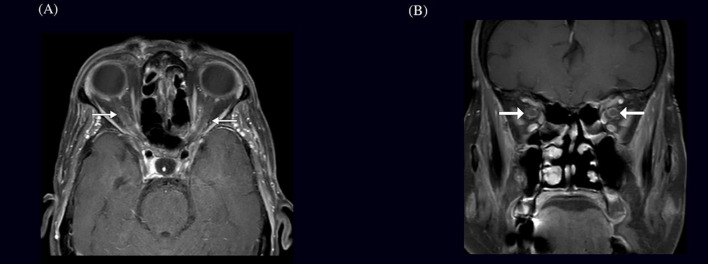

Case presentation: This case study reports a 75-year-old female presenting with subacute constitutional symptoms of fever and poor appetite with bilateral eye pain and visual disturbance. The patient had elevated inflammatory markers, specifically an erythrocyte sedimentation rate of 120 mm/h, with imaging findings consistent with bilateral OPN and temporal artery biopsy-proven GCA. Treatment with high-dose dexamethasone, followed by oral prednisolone and tocilizumab, led to symptomatic improvement in vision stabilization.